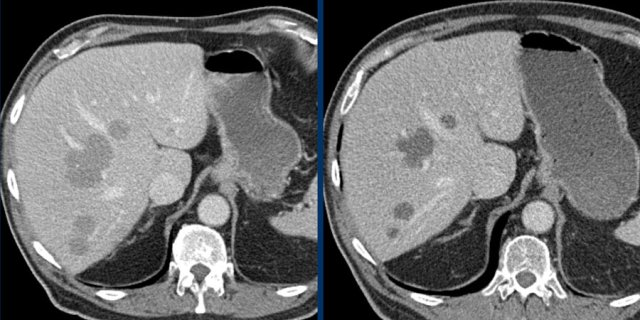

The CT image of the liver of a 96-year-old male with HCC in the late arterial phase shows a hypervascular tumour in the right liver lobe (arrowheads).

The tumor is well delineated from the surrounding parenchyma.

In the portal-venous phase the HCC is hardly distinguishable from the liver parenchyma due to early washout of contrast.

This HCC is suitable for mRECIST.